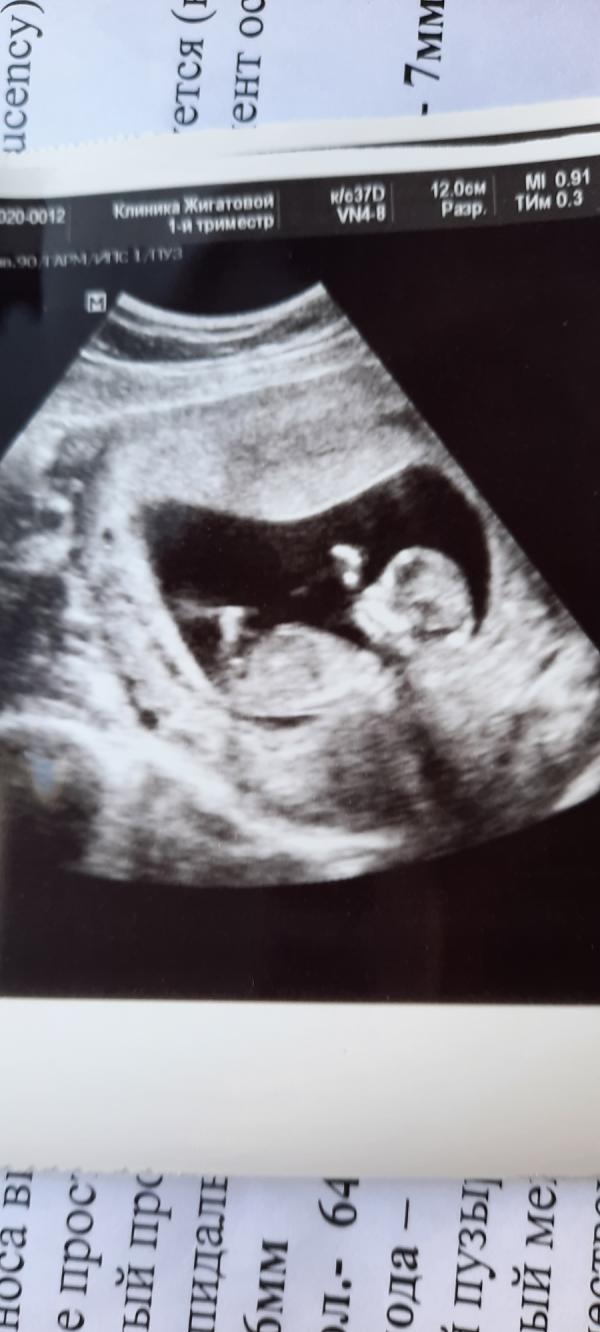

А вот и наше первое фото #машааллах 🥰🙏 всё у нас хорошо,слава Богу 🤲Правда у меня был сильный гипертонус , не видели вообще ничего , попросили вставить папаверин,выпить ношпу, покушать хорошенько,а потом вернуться на УЗИ . Ну я так и сделала , когда вернулась , тонуса небыло уже , всё прекрасно видно было 😘 в общем вот так 😍 пол не знаю ещё , через 5 дней должна повторить УЗИ и пол сразу скажут 🥰

#12недель #узи #первоефото #беременность #3месяца #2триместр #многодетная #ждумалыша#скрининг#1скрининг

Да, скриниг будет не иноформативен. Поздравляю, что увидели своего малыша. Но через 5 дней будет только предположение кто у вас. Т. К. Половые органы Формировываюс в 16 недель. А пока бугорок половой который одинаков что у девочки что у мальчика. Только небольшой угол наклона отличает.